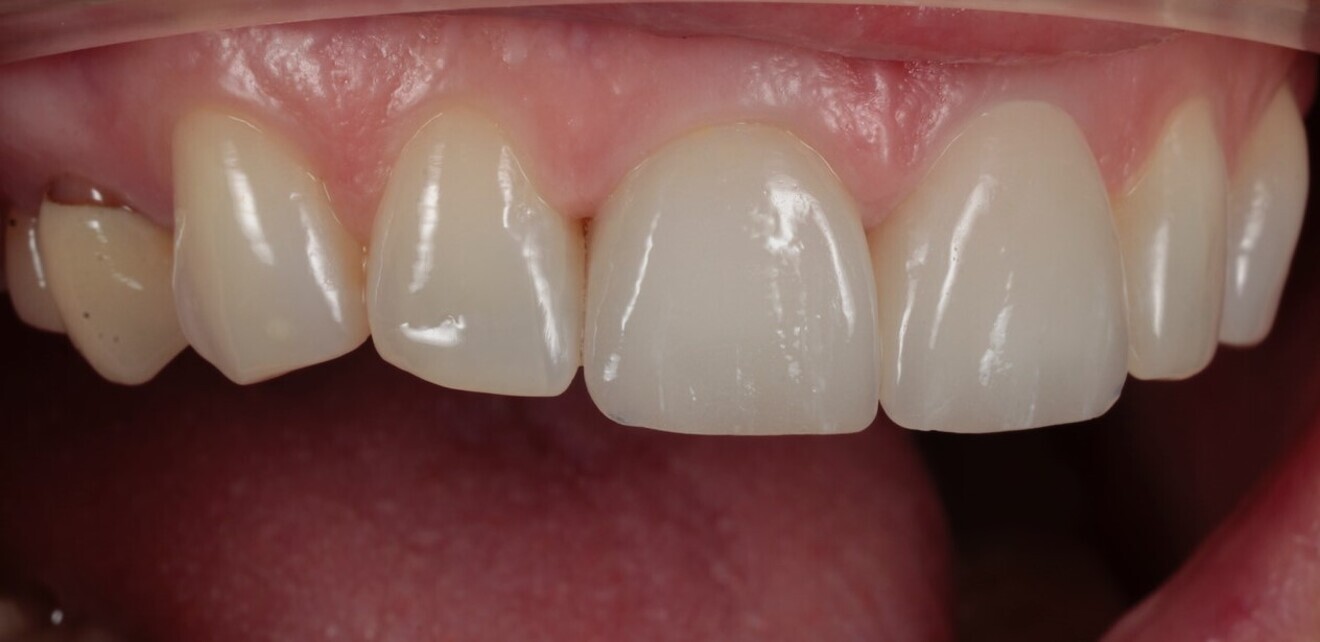

A 48-year-old female patient came to see me in 2004. The patient initially presented because she was unhappy with her two discoloured maxillary central incisors (Fig. 1). She also had chipping and wear of the mandibular teeth and broken posterior bridgework. Her “bite” also felt uncomfortable (Fig. 2).

Fig. 1: 2004—discoloured maxillary central incisors.

Discoloured maxillary central incisors. (All images: Tif Qureshi)